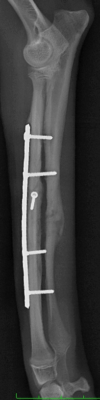

右前肢

左前肢

*写真なので写りこみをカットしています。

橈骨・尺骨ともに癒合してますし、

橈骨の髄腔もきちんと確認できます。

極端な骨硬化像も認めないので経過観察終了としました。

その後、紹介いただいた先生もとで去勢手術と同時にネジの間引きを実施しています。

螺子(ネジ)の間引きだけなら術後の安静も外固定も必要ありません。